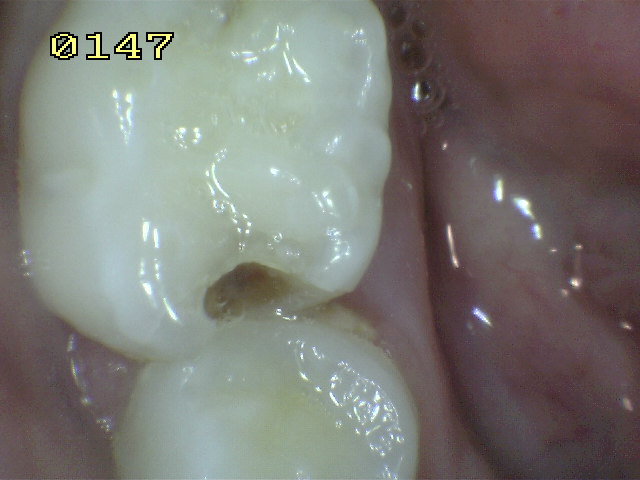

Código 4

(Caries Moderada): Sombra oscura

de dentina subyacente al esmalte intacto con o sin interrupción

localizada del esmalte

-

Esta lesión aparece como una sombra de decoloración

visible a través de una superficie de esmalte intacta, la que puede o no mostrar signos

de descomposición localizada del esmalte, como la microcavidad y /o discontinuida

< 0,5mm. después del secado con aire durante 5

segundos

La aparición de

la sombra se ve a menudo con más facilidad cuando

el diente está húmedo. El área oscura es una

sombra intrínseca que puede aparecer gris, negro-azul o

marrón-anaranjado,

a través de las paredes del esmalte vestibular, lingual o

palatino